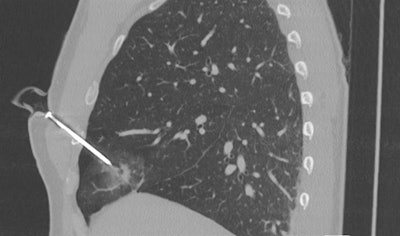

- Lungs: CT is highly sensitive for pneumothorax as well as other pathology in patients with penetrating trauma that clinicians may easily miss on x-ray, such as pulmonary contusion and laceration.